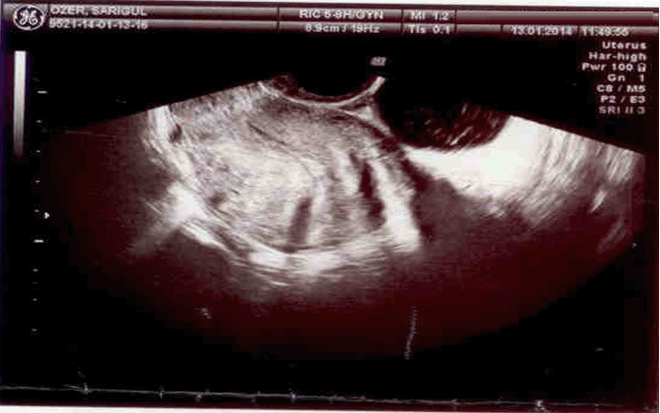

A 21-year-old female admitted into emergency room of Agri Obstetrics and Gynecology Hospital with syncope, nausea, emesis and vaginal hemorrhaging in staining character. She was not having her period for 2 months and was diagnosed with anembryonic pregnancy in another private medical clinic. Eight hours before admission, the patient was treated with dilatation and curettage (D&C) under elective conditions in the same medical clinic she was diagnosed without any complications and the patient was discharged after the operation. Postoperatively 8 hours, the patient gradually started to feel unwell and finally was brought to the emergency room of our hospital. The medical history stated that this was her first pregnancy and she had no history of a coexisting illness or medication. Following admission, no active hemorrhage was diagnosed during speculum inspection but routine hemorrhage in staining character was common following such procedures. Abdominal examination showed a widely distributed tenderness in all quadrants during palpation and rebound finding was prominent in lower quadrants. Dyspnea and palpitations were seen in supine position. Ultrasonography (USG) examination showed a normal uterus, endometrium thickness (10 mm) and normal bilateral ovary structures. Disseminated dense fluid retention in a hemorrhagic fashion was detected in Douglas and paraovarian areas in addition to intestinal segments. The image was consistent with an embryo in yolk sac with a gestational age of 6 weeks and six days in ampullar portion of right fallopian tube. (Figure 1) and (Figure 2). The patient vital signs were blood pressure 80/40 mmHg, pulse 98/minute and hemoglobin was 7.8 g/dl, HTC 22, Platelet count 182000 and WBC 14000. Patient was closely followed and the USG images taken before D&C procedure were obtained from the patient. The images revealed a gestational sac consistent with an anembryonic pregnancy measuring 33 mm located in uterine fundus and the procedure was actually a D&C for abortion (Figure 3) and (Figure 4). Patient's relatives were notified of the medical situation of the patient and our initial diagnoses were either a uterine rupture or a coexisting pregnancy of a heterotopic type. Laparotomy was planned after assessment of the clinical situation of the patient and risks and details of the procedure was shared with the patient. After obtaining 3 units of erythrocyte suspension, the abdominal access was done using a Pfannenstiel incision. Dense disseminated fluid was detected and about 2 liters. of this hemorrhagic fluid was aspirated. After aspiration, no signs of perforation was found on the front or rear surface of the uterus. In tubal structures inspection, left tube and ovary was normal but right tube had an actively bleeding gestational sac about 2 cm in diameter on ampullary portion and a full thickness perforated tubular structure confirmed our diagnosis of heterotopic pregnancy (Figure 5). Salpingostomy was chosen after considering patient's age and gravidity. The tube was repaired using 3–0 Prolene sutures after removal of all trophoblastic structures. Operation was finished after checking for hemorrhage and an abdominal drainage tube was inserted for follow-up. Three units erythrocyte suspension was used during the operation. Within 48 hours in postoperative period, 50 cm3 serohemorrhagic fluid was collected in the drain. The abdominal drainage tube was removed on the third day of operation and patient was discharged from the hospital with full recovery. The patient was advised to go to regular follow-up in gynecology and obstetrics clinic. b-hCG values dropped below 5 and no complications were seen in incisional scar area. She was also informed about the possible risks that might occur in future pregnancies.

Figure 3: Intrauterine anembryonic sac consistent with 8 weeks (before D&C).